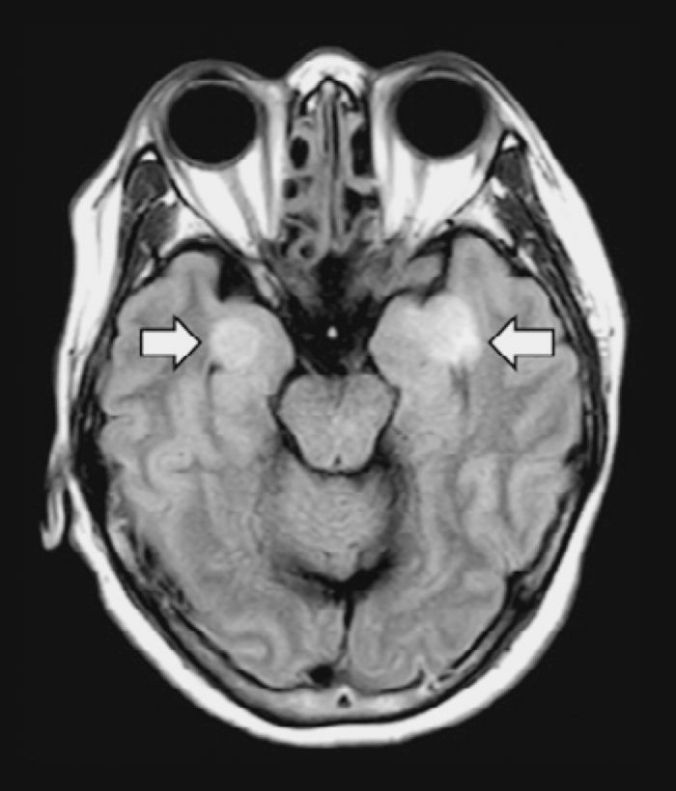

cor 3Uma mulher de 58 anos com COVID-19 desenvolveu encefalite, resultando em danos nos tecidos do cérebro (setas). N. POYIADJI ET AL., RADIOLOGY, (2020) DOI.ORG/10.1148/RADIOL.2020201187

Os receptores ACE2 estão presentes no córtex neural e no tronco cerebral, diz Robert Stevens, médico intensivista da Johns Hopkins Medicine. Mas não se sabe em que circunstâncias o vírus penetra no cérebro e interage com esses receptores. Dito isto, o coronavírus por trás da epidemia de síndrome respiratória aguda grave (SARS) de 2003 – um primo próximo do culpado de hoje – pode se infiltrar nos neurônios e às vezes causar encefalite. Em 3 de abril, um estudo de caso no International Journal of Infectious Diseases, de uma equipe do Japão, relatou traços de novos coronavírus no líquido cefalorraquidiano de um paciente com COVID-19 que desenvolveu meningite e encefalite, sugerindo que também pode penetrar no sistema nervoso central.

Mas outros fatores podem estar danificando o cérebro. Por exemplo, uma tempestade de citocinas pode causar inchaço no cérebro, e a tendência exagerada do sangue para coagular pode desencadear derrames. O desafio agora é mudar de conjectura para confiança, em um momento em que a equipe está focada em salvar vidas e até mesmo em avaliações neurológicas, como induzir o reflexo de vômito ou transportar pacientes para exames cerebrais que correm o risco de espalhar o vírus.